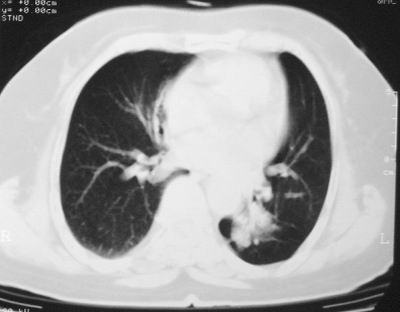

患者,女,64岁,4年前左腮腺"多形性"腺瘤手术治疗史.现复查胸部ct见左下肺块状影,该影与原左腮腺手术是否有联系?

本次复查胸部ct

左下肺软组织块影,有分叶、毛刺、空泡及胸膜牵拉征,左下肺周围性肺癌。

左肺下叶周围型肺癌,支持!(软组织肿块+分叶+毛刺+空泡+胸膜凹陷征)

左下肺软组织密度影,可见分叶,边缘可见毛刺征,胸膜增厚,强烈要求左下肺周围型肺癌

左下肺后基底段实性肿块,周围有毛刺,病变周围有肺气肿,与降主动脉间有条带状影相连,病灶4年前查体发现,纵隔内未见肿大淋巴结。考虑.肺隔离症,建议增强扫描与周围型肺癌鉴别。